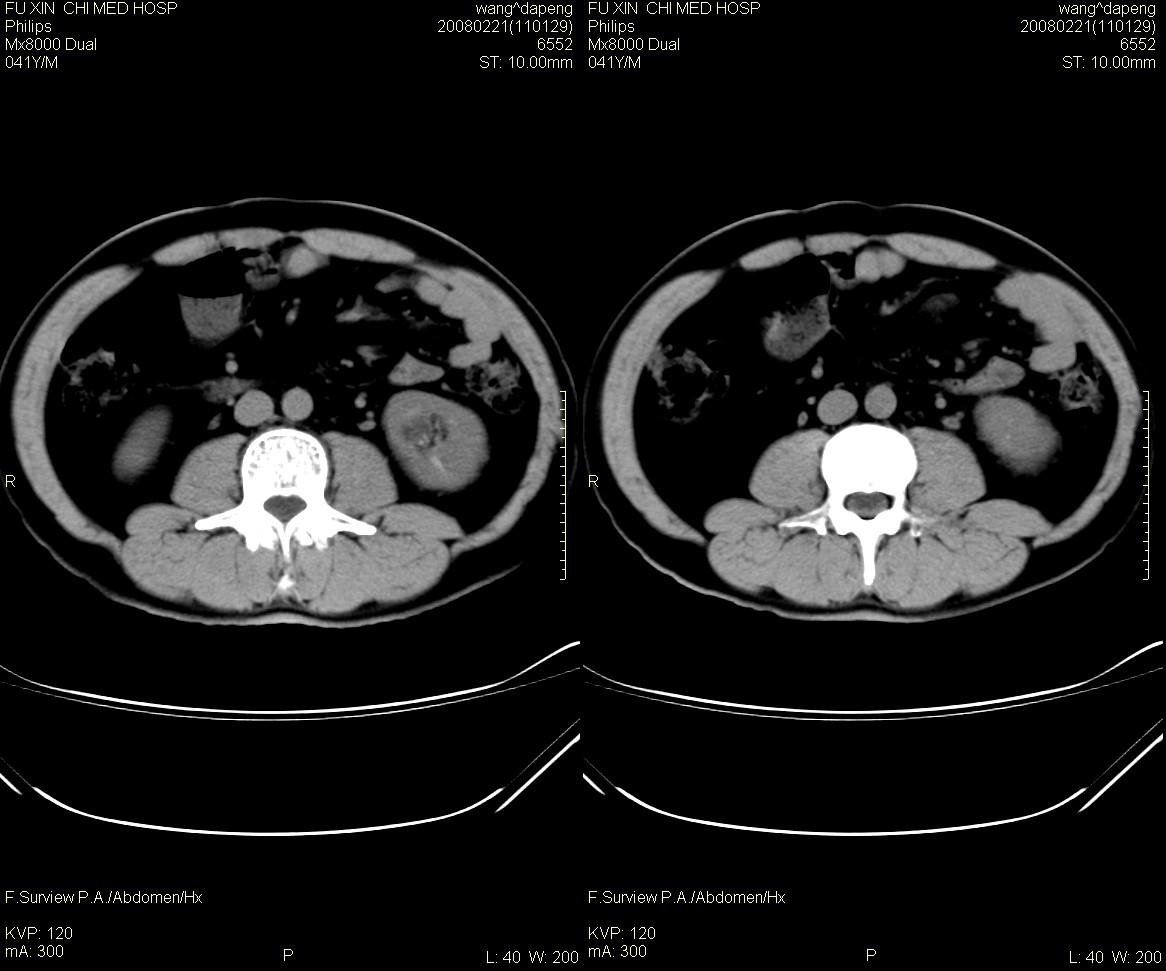

髓质海绵肾是一种先天性的肾髓质囊性病变, 其特征为肾锥体部乳头管及集合管呈梭形或囊状扩张,并伴发感染和尿路结石形成。在肾标本切面上, 可见髓质中呈海绵状改变。ct平扫表现为肾盏旁锥体内多发小斑点状结石, 成扇形排列.增强扫描后扩张的肾集合管内结石周围有造影剂充盈, 无结石的肾锥体集合管呈条纹状或小囊状造影剂积聚,肾功能正常.

海绵肾是先天性的,可能是有遗传倾向的良性肾髓质囊性病变,常于40岁以后发现,易误诊断肾结石和尿路感染。其病理特征是肾小管远端集合小管扩张,形成小囊和囊性空腔,并位于肾盏连接处,易导致结石、感染等。病变一般为双侧性80%的病人部分或全部肾乳头受累。临床上病变局限,轻微者可无明显症状,常见的症状为腰痛、血尿、尿路感染及肾绞痛等。

海绵肾的影像诊断主要靠静脉尿路造影,在平片上表现为双侧肾盏处侧有多发的小结石影。造影后显示肾乳头囊状扩张,内见单发或多发的钙化点,表现为环绕于肾盏、肾盂周围的多数囊腔,形似菜花。ct对海绵肾集合小管囊状扩张的空间分辨率不如ivu高,但对检出其中的小结石较x线敏感。因此,可疑海绵肾的影像诊断应结合上述两种检查。

肾盏远端多发点状骨密度影;肾实质细管点壮水密度影;海绵肾须考滤